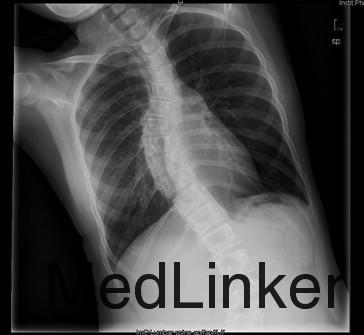

患者女,13岁,因“发现脊柱侧凸畸形4月”入院。患者4月前家长无意间发现胸背部脊柱侧凸,双肩不等高,无牛奶咖啡斑、无皮下结节,不伴活动耐力下降、气促、心悸、胸背痛、腰痛,日常活动及运动能力正常,在当地医院检查后建议手术治疗,到我院就诊,门诊以"特发性脊柱侧凸"收入住院。

查体:胸段脊柱向右侧凸,右侧胸廓后部凸起,剃刀背畸形,剃刀背高度2cm,右肩高,骨盆略向右倾斜,四肢及关节未见异常,未查见牛奶咖啡斑。脊柱各棘突及棘突旁无压痛及扣痛。胸腰部前屈、后伸及侧屈、侧旋范围正常,双下肢等长,未发现感觉减退区,四肢肌力5级,生理反射均正常引出,病理反射未引出。 辅查:X片示胸段脊柱以胸8为中心明显右侧弯畸形,胸段上段及腰段相应轻度左突侧弯。

初步诊断:特发性脊柱侧凸(Lenke:ⅡA ̄型) 诊疗计划: 拟经后路脊柱侧凸矫形+同种异体骨植骨+椎弓根螺钉内固定术术

术中见胸椎脊柱S形侧弯,肌肉韧性较差,棘突偏离中线,凹侧小关节退变明显,胸段脊柱以T8为中心明显右凸,T4为中心向左侧凸起,右侧剃刀背畸形。